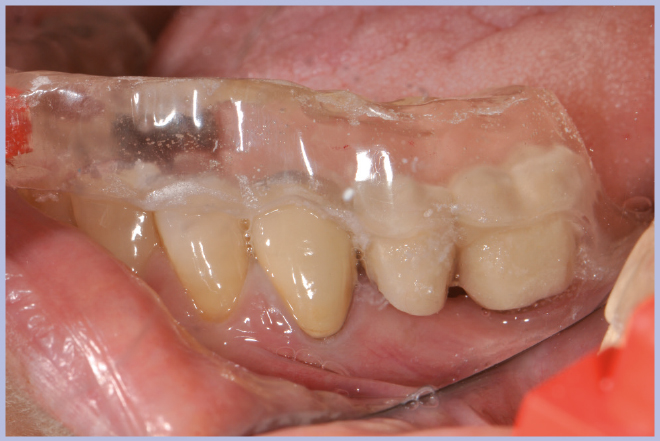

- Figg. 6, 7 – Verifica clinica della stabilità della mascherina radiologica sulla paziente

- Fig. 7